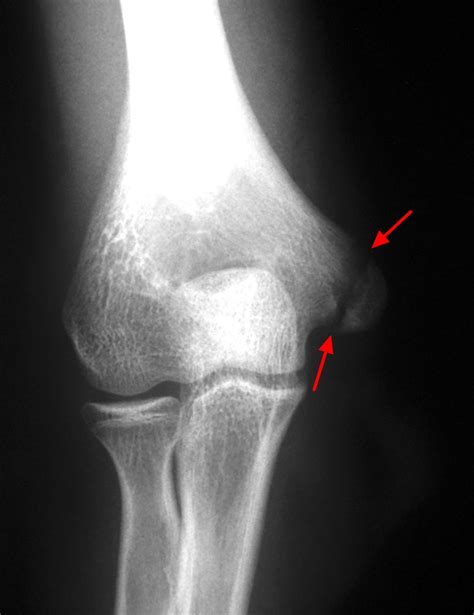

• X-ray Imaging: The primary tool for diagnosis, though it is important to note that growth plates can be difficult to see on standard X-rays, often requiring comparisons to the uninjured limb.

• growth plate fracture xray